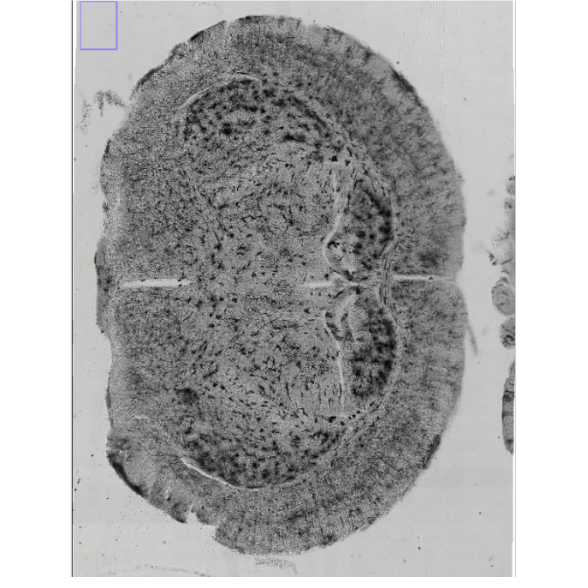

針對活體動物模型,雙光子顯微鏡通過長波長激光穿透生物組織,實現(xiàn)哺乳動物胚胎大腦皮層內神經(jīng)元與膠質細胞的實時觀測。2025年清華大學團隊開發(fā)的IMEE技術,結合雙光子成像與子宮內固定裝置,首次在體闡明了抑制性神經(jīng)元遷移與血管網(wǎng)絡、小膠質細胞的動態(tài)互作模式。研究發(fā)現(xiàn),抑制性神經(jīng)元通過“末端接觸”或“突起接觸”與血管相互作用,其中末端接觸引發(fā)引導突分支收縮,而突起接觸允許神經(jīng)元沿血管壁滑動遷移。

在數(shù)據(jù)解析層面,CellAnalyzer Pro通過集成三維點云分析模塊,可自動重建神經(jīng)元遷移軌跡與血管拓撲結構,并計算接觸頻率、持續(xù)時間等動態(tài)參數(shù)。例如,在自閉癥模型小鼠中,系統(tǒng)發(fā)現(xiàn)抑制性神經(jīng)元與血管的異常接觸模式(接觸時間縮短32%,分支收縮頻率增加45%),為早期干預靶點篩選提供量化依據(jù)。